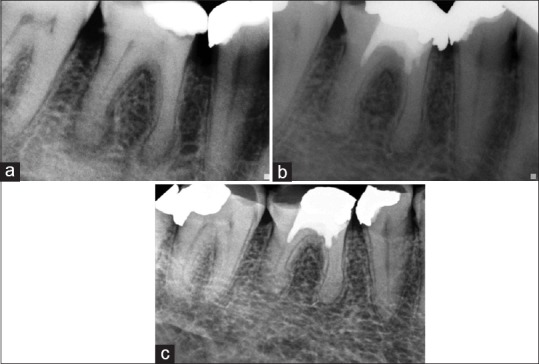

Figure 3.

(a) X-ray showing large periapical lesions associated with teeth #36 and 37 in a 17-year-old girl. (b) SealBio was performed in both the teeth. The second molar required post and core restoration due to severe coronal destruction. Follow-up radiograph at 2-year showing significant healing (compare with Figure 4a). (c) Follow-up at 3-year shows normal bony architecture around both the root apices